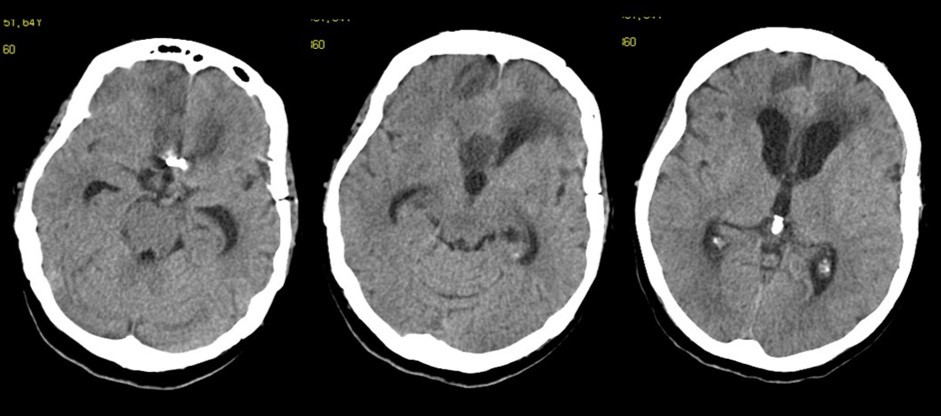

A 65 years-old woman with no relevant medical history was carried to the emergency department of another institution for the sudden onset of headache and vomiting, followed by loss of consciousness. She underwent a cerebral CT scan, that showed diffuse SAH in the basal cisterns and anterior interemispheric fissure (Figure 1). The CT angiogram displayed a single aneurysm of the anterior communicating artery, that local radiologists considered unfavorable for endovascular treatment. The patient was therefore surgically managed, with left pterional craniotomy for aneurysm clipping and right external ventricular drain (EVD) positioning. In the following days the woman reacquired alertness; the EVD was removed without need of permanent shunting and she was transferred to rehabilitation four weeks after the operation in quite good conditions.

Figure 1.Non-contrast axial CT scan showing thick subarachnoid hemorrhage in the basal cisterns and in the frontal interemispheric space